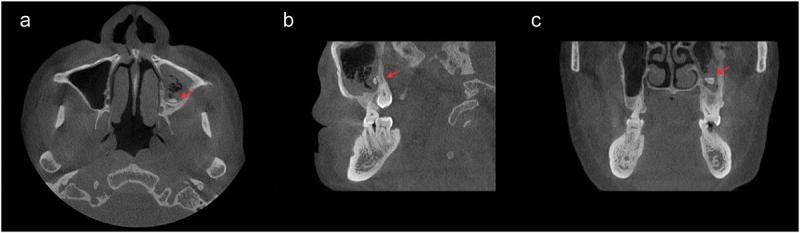

This case reports a 70-year-old male patient who developed an odontogenic brain abscess secondary to periodontal infection and underwent neurological surgery. Extract pus during surgery for the metagenomic next-generation sequencing (mNGS).

The mNGS of pus samples obtained from brain abscess aspiration identified the periodontal pathogens and . Consequently, he was referred to the department of stomatology for further examination and treatment.

本病例报告了一名70岁男性患者,因牙周感染继发牙源性脑脓肿并接受了神经外科手术。术中抽取脓液进行宏基因组下一代测序(mNGS)。

从脑脓肿穿刺抽取的脓液样本进行mNGS检测,鉴定出牙周病原体和。因此,他被转诊至口腔科进行进一步检查和治疗。